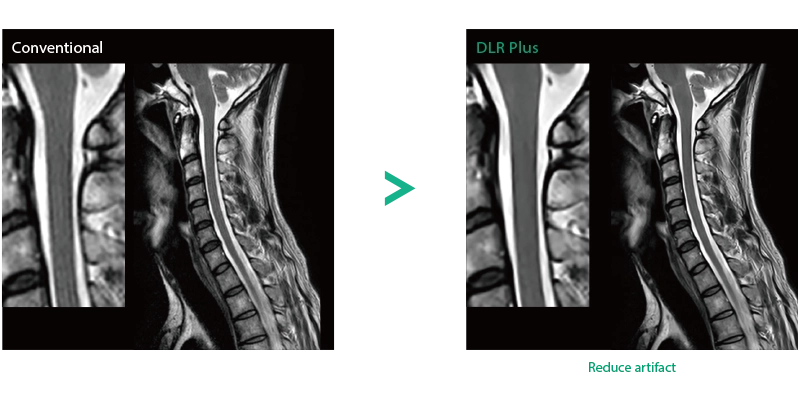

Deep Learning technology*8 enables image quality adjustment after imaging is complete. It optimize SNR and improve image sharpness by processing MRI signals in stages (k-space signal processing). This brings super-resolution and reduces truncation artifacts.

- *8 Deep Learning is used for the development. The performance and accuracy of the device will not automatically change after installation